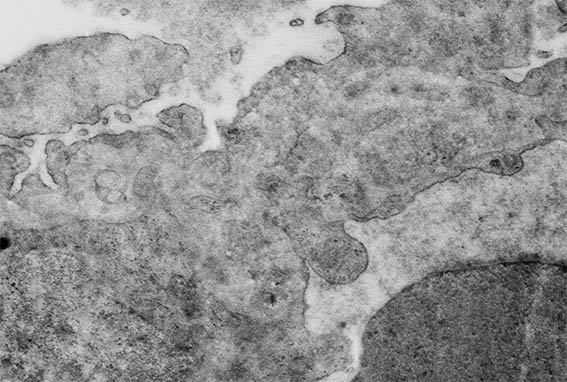

Figure 12. Electron microscopy, original magnification, X4,000. Segmental damage of the capillary wall, with a double contour.